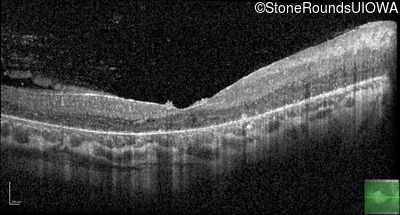

Optical Coherence Tomography - Right - 20/160

Exemplar / OCT Stack